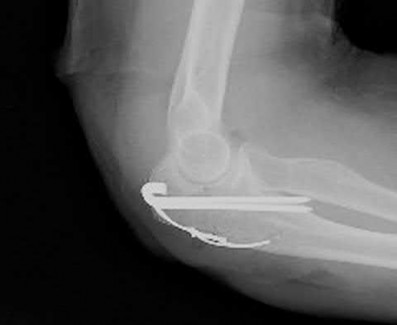

A 24-year-old woman is thrown from her motorcycle and sustains the closed injury shown in Figures A through C. Open reduction and internal fixation is planned. What surgical technique will best allow visualization of the joint surface and allow early range of motion?

Access to complex intra-articular fractures is best achieved by an olecranon osteotomy (OO). Fixation can be with parallel plating or orthogonal plating.

Bicolumnar fixation of distal humerus fractures should follow the principles outlined by O'Driscoll: Distal fragments should be held by as many screws as possible; every screw in the distal fragments should pass through a plate; each screw should engage as many articular fragments as possible.

Galano et al. review treatment for bicolumnar distal humerus fractures. They note that the olecranon osteotomy, Alonso-Llames triceps sparing and Campbell triceps splitting approaches expose 57%, 46% and 35% of the articular surface, respectively. The OO and paratricipital (triceps sparing)

approaches allow for early ROM. Protected motion is required for the O'Driscoll TRAP and Bryan-Morrey approaches for tendon-to-bone healing.

Figures A and B show a AO/OTA type C2 intraarticular distal humerus fracture. Figure C is a coronal CT scan showing intraarticular comminution. Illustration A shows fixation of the fracture with bicolumnar plating through an olecranon osteotomy approach. Illustration B shows the various approaches to the distal humerus (left, Campbell triceps splitting; center left, O'Driscoll triceps reflecting anconeus pedicle; center right, Bryan-Morrey approach, leaving the triceps attached laterally to the fasciocutaneous flap, but elevating it off the ulna; right, olecranon osteotomy). Illustration C shows 3 methods of olecranon osteotomy (A and B, Intra-articular transverse; C-F, Extra-articular oblique; G, Intra-articular chevron).